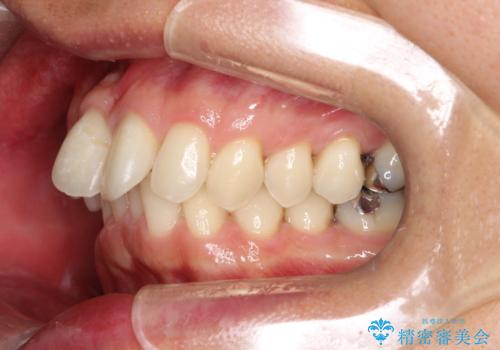

【遠心移動ワイヤー矯正】翼状捻転を治したい

今回は患者さんの希望もあり非抜歯にて歯列拡大、遠心移動を行なってできる限り前歯を下げながら配列する治療を行いました。

上顎はリンガルアーチにて遠心移動を行うことで前歯を唇側傾斜させずに配列することができました。